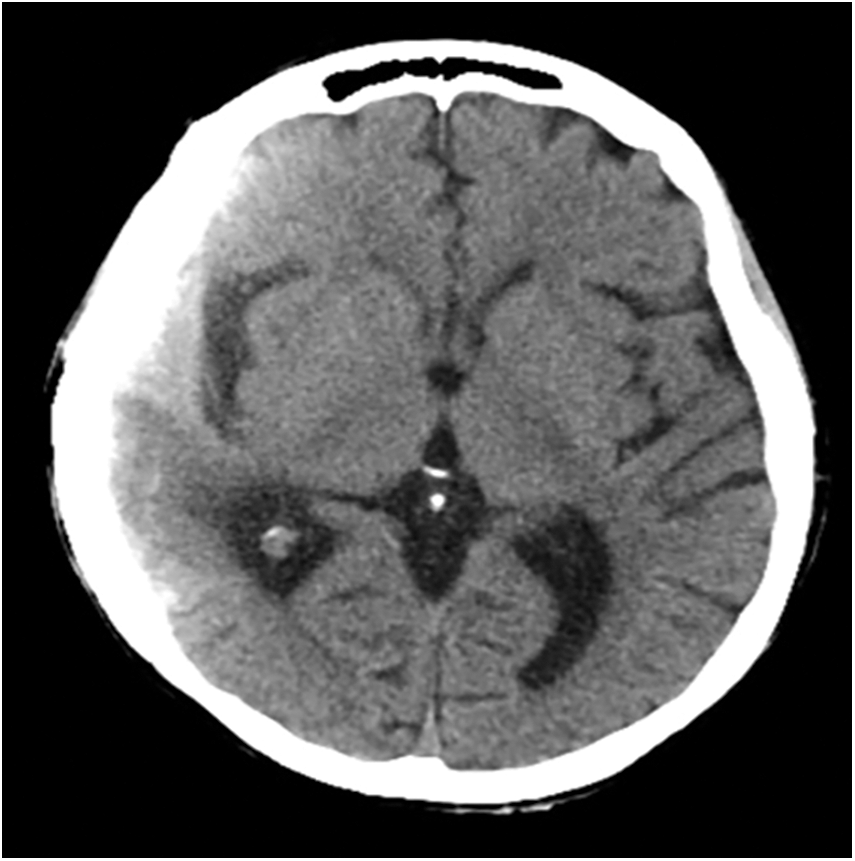

A whole body 18-FDG PET/CT scan was subsequently performed, revealing no tracer uptake (Figs. 2A, 2B). Postoperative brain CT and MRI scan showed a complete removal of the lesion (Figs. 3A, 3B). The patient progressively improved, most notably after performing hydroxyapatite cranioplasty (Fig. 4). The patient was discharged on postoperative day 20 and transferred to the radiation oncology unit for the adjuvant treatments.

Figure 4: Postoperative brain axial CT scan performed after hydroxyapatite cranioplasty